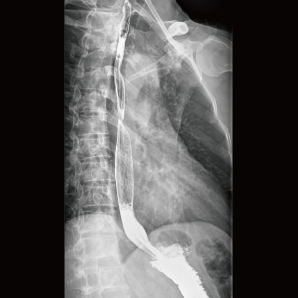

l 数字化造影

可以进行对比研究,例如食管造影、静脉肾盂造影和输卵管造影

l 床体倾斜

床体的大角度倾斜范围,全面匹配数字化造影摆位